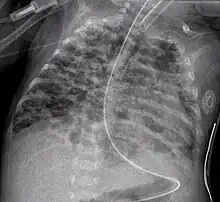

Chest film showing increased opacity in both lungs, indicative of pneumonia